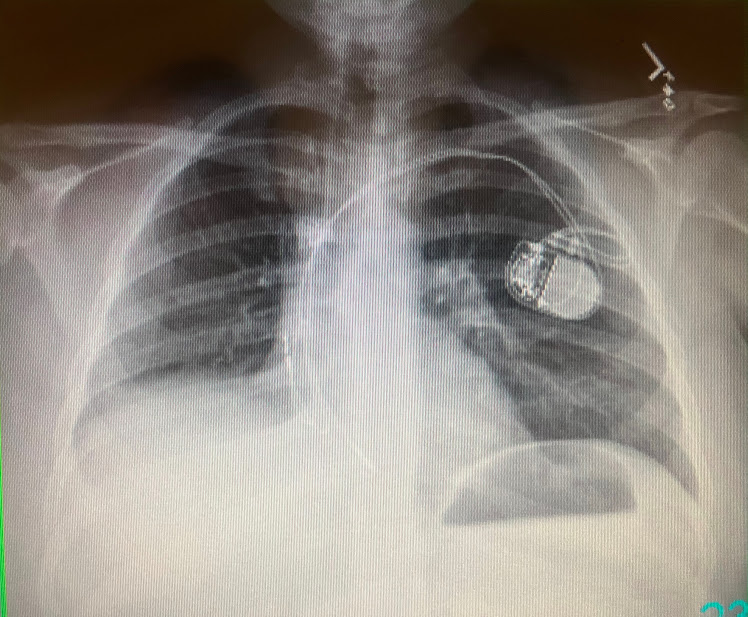

The cancer spread to the pleural lining. It has spread to four of the lymph nodes they’ve tested as well.

They now type my cancer as Stage IIIA.

Quite a difference from Stage I. Instead of completing treatment with surgery, surgery begins treatment.